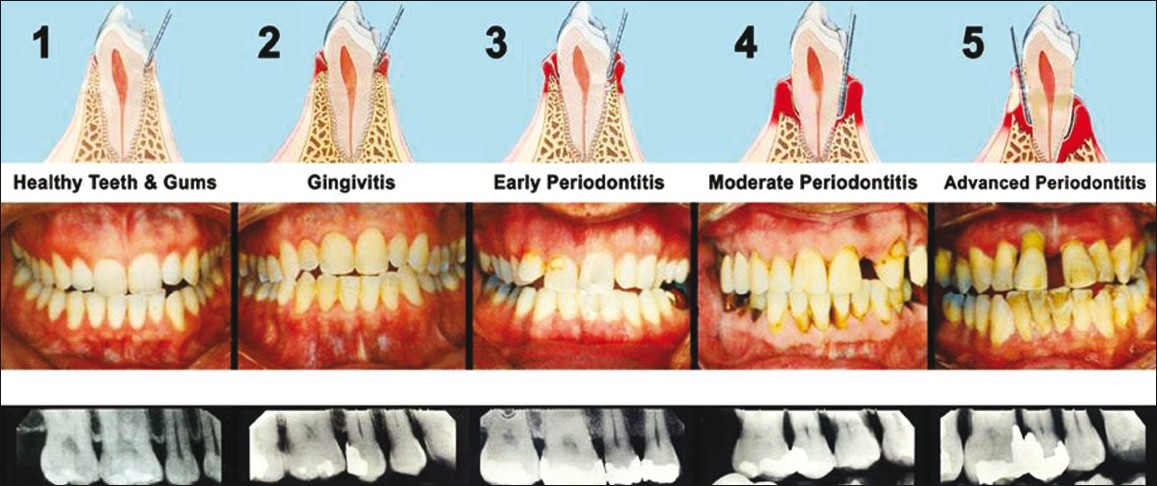

What is periodontal disease?

What are periodontal diseases? Periodontal disease is an infection in the areas around the teeth, but not in the teeth. Gingivitis is usually the first stage of periodontal disease which can progress and effect other structures in the mouth.

What is the first stage of periodontal disease?

The first stage of periodontal disease, called gingivitis, only affects the gums. Symptoms of gingivitis may include bleeding and swollen gums, bad breath, pain when chewing, and recession of the gums. If left untreated, gingivitis can advance to the other structures in the mouth and overtime, cause tooth or bone loss.

Treating periodontal disease is usually broken down into three phases. The first phase is focused on minimizing the risks that may have caused the infection, controlling the infection, and learning how to take care of your oral care to stop the progression of the infection.

How many phases of periodontal disease?

According to the National Institute of Dental and Craniofacial Research, it’s caused by poor oral hygiene, smoking, chronic illnesses or using certain medications.

Because periodontal disease can increase your risk for conditions such as stroke, heart disease, diabetes, and respiratory diseases, it’s critical to treat it. Starting the treatment early can help you avoid requiring the more invasive treatments later on.